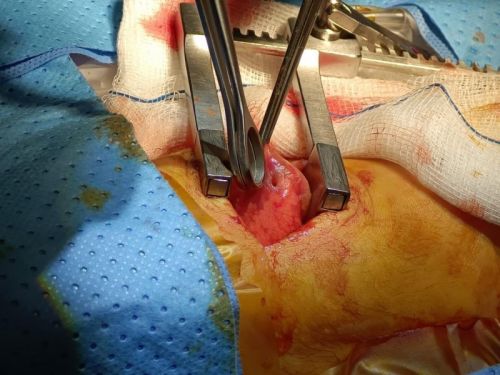

曾嘉航主任和范世豪主任探查胸腔打开胸腔后,曾嘉航主任和仁伯爵医院范世豪主任2分钟内精准锁定3处瘘口,用显微缝线将其严密闭合。这场历时20分钟的床边手术顺利完成,终于患儿血氧趋于稳定,胸腔引流瓶不再出现气泡,床边胸片提示右肺复张良好,“生命修补战”终告捷报。术后第四天,患儿恢复顺利,已顺利拔除胸腔引流管。

术中探查右肺下叶瘘口仁心无界:特别的生命守护者手术结束后,患儿父亲满怀感激,紧紧拥抱着曾嘉航主任放声大哭道:"结婚7年以来,之前的两个孩子都因各种原因自然流产,这个孩子承载着我们全部的希望。"